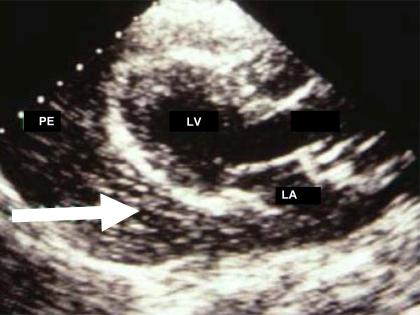

Bedside echocardiography in emergency room (ER) or in intensive care unit (ICU) is an important tool for managing critically ill patients, to obtain a timely accurate diagnosis and to immediately stratify the risk to the patient's life. It may also render invasive monitoring unnecessary. In these patients, contrast echocardiography may improve quality of imaging and also may provide additional information, especially regarding myocardial perfusion in those with suspected coronary artery disease. This article focuses on the principle of contrast echocardiography and the clinical information that can be obtained according to the most frequent presentations in ER and ICU.

急诊室(ER)或重症监护病房(ICU)中的床旁超声心动图是管理危重症患者的重要工具,有助于及时准确地做出诊断,并立即对患者的生命风险进行分层。它还可能使侵入性监测变得不必要。对于这些患者,超声造影可提高成像质量,还可能提供额外信息,尤其是对于疑似冠心病患者的心肌灌注情况。本文重点介绍超声造影的原理以及根据急诊室和重症监护病房中最常见的表现所能获得的临床信息。